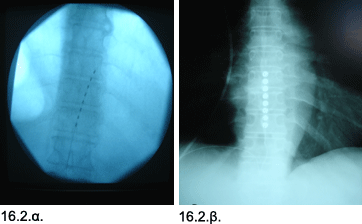

Εικόνες 16.2.α. & 16.2.β. Απλή ακτινογραφία δείχνει την διαδερμική τοποθέτηση του κυλινδρικού ηλεκτροδίου προσωρινής δοκιμαστικής επισκληριδίου διέγερσης νωτιαίου μυελού (16.2.α.) και την ελάχιστα επεμβατική τοποθέτηση ηλεκτροδίου σε μορφή λωρίδας για μακροχρόνιο επισκληρίδιο διέγερση νωτιαίου μυελού (16.2.β.).

Η ασθενής υποβλήθηκε σε δοκιμαστική ηλεκτρική διέγερση νωτιαίου μυελού με κυλινδρικά ηλεκτρόδια και ο πόνος μειώθηκε από τον βαθμό 8/10 στο βαθμό 4/10 στην στην Κλίμακα Πόνου VAS (Visual Analog Scale). Μετά την επιτυχή δοκιμαστική διέγερση, η ασθενής υποβλήθηκε σε ελάχιστα επεμβατική τοποθέτηση χρονίου ηλεκτροδίου επισκληριδίου ηλεκτρικής διέγερσης νωτιαίου μυελού, σε μορφή λεπτής λωρίδας, το οποίο αποδείχθηκε ακόμη πιο αποτελεσματικό, μειώνοντας τον πόνο από τον βαθμό 8/10 στον βαθμό 3/10 στην Κλίμακα Πόνου VAS (Visual Analog Scale). Το ικανοποιητικό αποτέλεσμα έχει διατηρηθεί, κατά τα επόμενα έτη, και η ασθενής κάνει ελάχιστη χρήση αναλγητικών φαρμάκων.